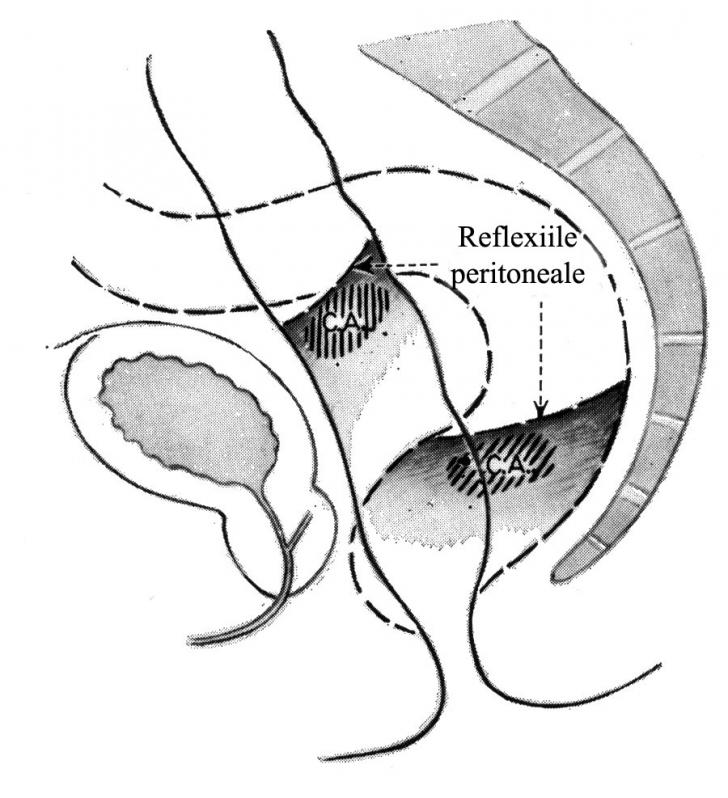

Contraindicatiile dializei peritoneale

Contraindicatiile dializei peritoneale Contraindicatii absolute : - Rezectii mezenterice intinse - Aderente peritoneale importante - Tumori abdominale mari - Ileus - Obezitate extrema - Comunicari pleuro-peritoneale largiCiteste tot ... 49 cuvinte

Dimensiune mica

- fara poza |